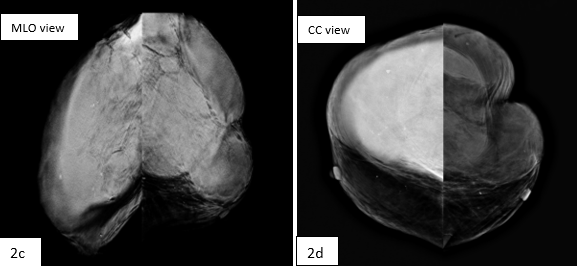

Fig 1a: Ultrasound shows coarse heterogenous liver parenchyma with surface irregularity & nodularity Fig 1b,c,d : CECT Imaging shows Small nodular cirrhotic liver with multi lobulated , well defined masses having mild heterogeneous post-contrast enhancement & few calcific foci in bilateral axilla and inguinal region. Hugely enlarged breasts partly seen in the scan. Ascites present. Fig 2 : 2D mammo (a,b) and Tomo images (c,d) of both breasts show bilateral high density large masses with smooth margins and no architectural distortion however few course heterogenous calcifications present randomly in breast parenchyma. (compromised scan quality is attributed to massive breast size) Fig 3 a,b,c,d : Ultrasound of bilateral breasts show iso to heteroechoic large breast masses occupying almost entire breasts. Normal breast tissue was compressed and difficult to identify. Colour doppler demonstrates significant vascularity within the masses. Fig 4 : Ultrasound of axillary lymph nodes. Fig 5 a,b : Biopsy from breast masses showed amyloid deposits (pink) predominantly around the ducts and blood vessels (a), demonstrated well on congo red stain (b).